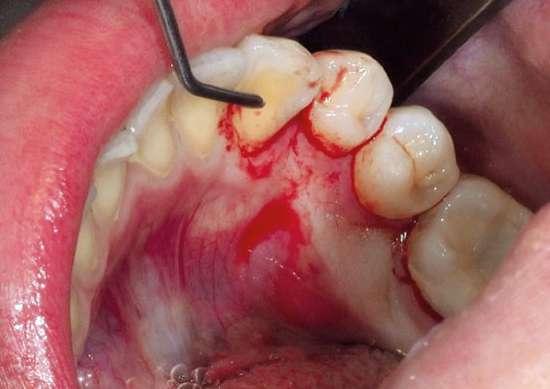

Dada la cercanía a las raíces de los dientes adyacentes y el riesgo de rizólisis de las mismas, se optó por realizar la exodoncia, utilizando para ello anestesia local de la zona (Fig. 2).

Tal y como se puede observar en las imágenes (Fig. 3 y 4) se realizó una incisión sulcular siguiendo el surco gingivodentario lingual sin descargas para despegar un colgajo a espesor total que facilitó un campo quirúrgico suficiente como para poder realizar la ostectomía hasta descubrir la corona del diente (Fig. 5).

La ostectomía se realizó de manera cuidadosa, tanto con el colgajo y las estructuras del suelo de boca, como con los dientes adyacentes y sus raíces. En este caso el diente no requirió odontosección, por lo que su exodoncia pudo ser completada usando un botador recto y unas pinzas adson para su retirada del alveolo (Fig. 6).

Una vez finalizada la intervención se procedió a realizar sutura interpapilar con sutura monofilamento 5/0 (Fig. 7 y 8).

Figuras 5 y 6. Ostectomía y exodoncia con botador tipo elevador recto.